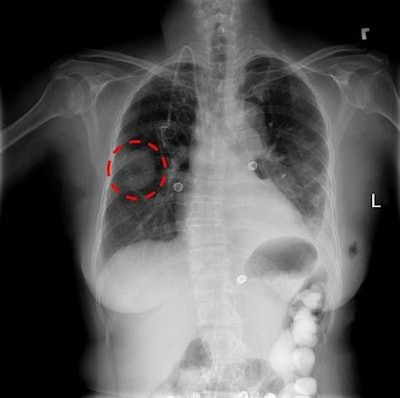

The NIH database includes more than 100,000 chest x-rays. Image courtesy of the NIH.

The database was created from studies of 30,000 patients who were seen at the NIH Clinical Center in Bethesda, MD; the information has been anonymized to protect patient identities. A number of the images are of patients with advanced lung disease, according to the NIH. The NIH Clinical Center is the country's largest hospital devoted entirely to clinical research, and patients who are seen there voluntarily agree to participate in clinical trials.

The NIH noted that interpreting a chest x-ray is a complex reasoning problem that "often requires careful observation and knowledge of anatomical principles, physiology, and pathology." These factors can make it more difficult to develop a consistent and automated technique for interpreting chest x-rays while also considering all possible thoracic diseases.